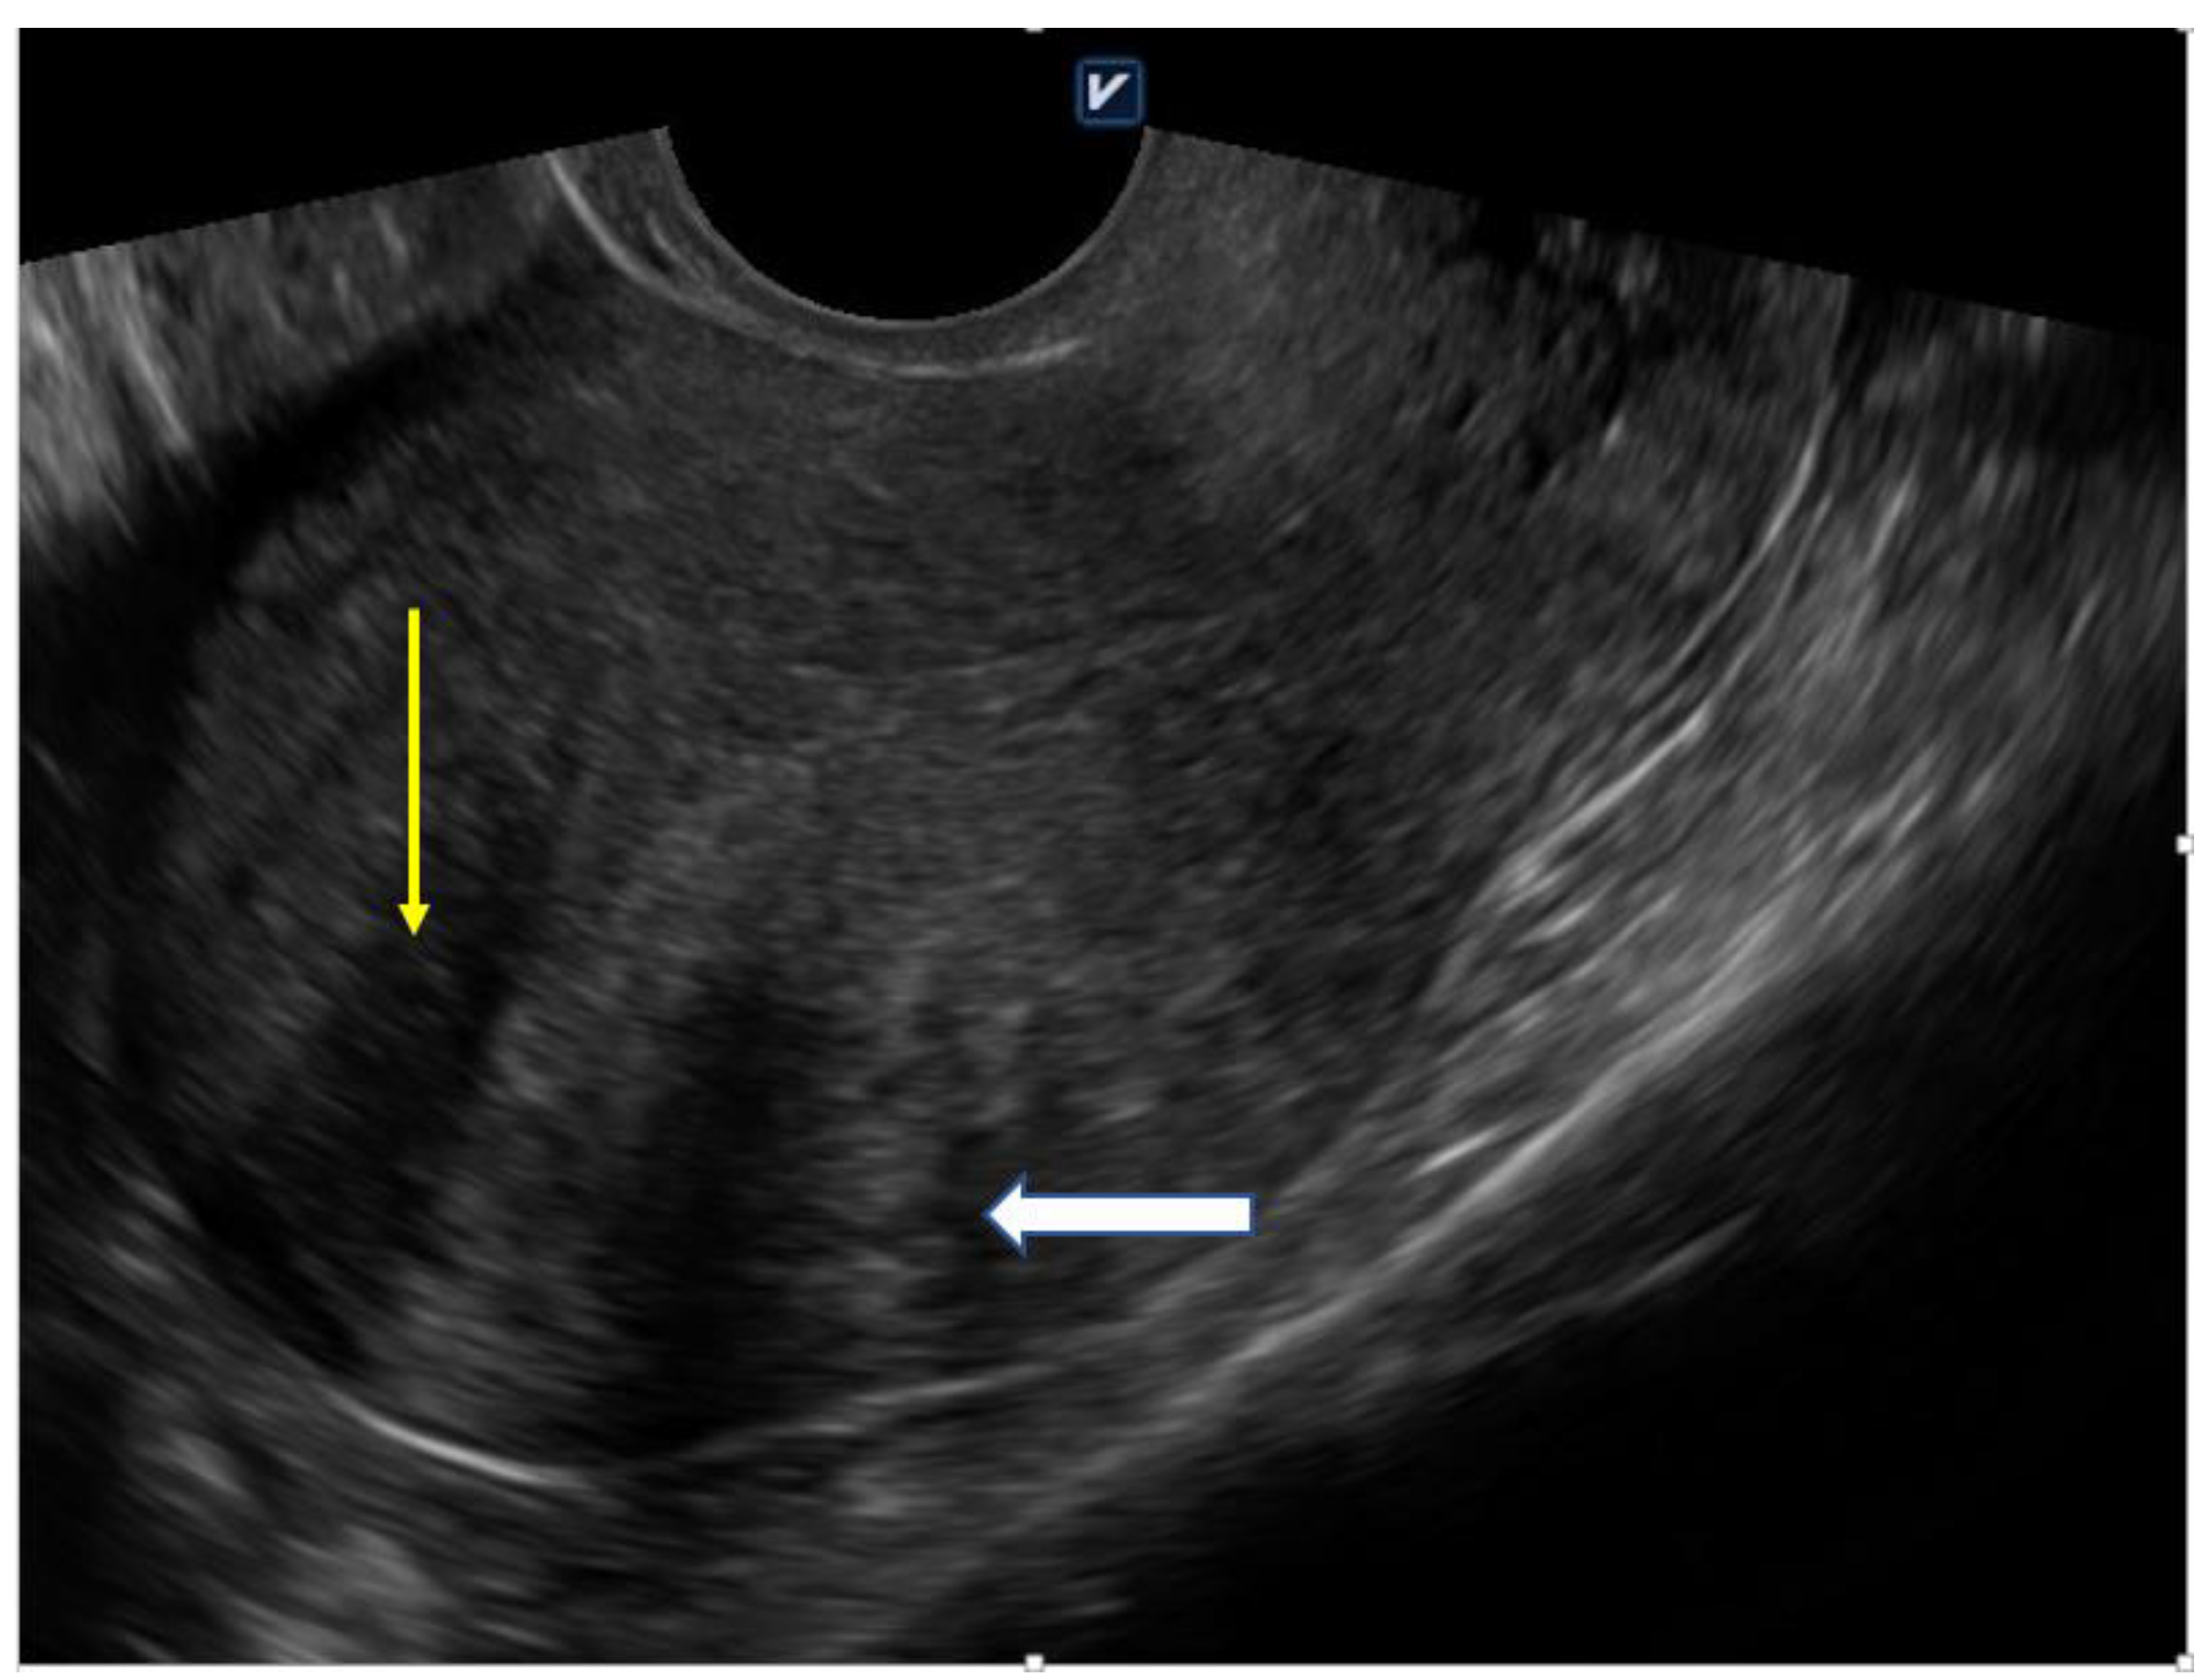

4.1. Ultrasound

| Diffuse Adenomyosis | Focal Adenomyosis |

| globally enlarged uterus | focal disturbances in myometrium layer |

| asymmetric thickness anterior and posterior wall = pseudo-widening sign | sometimes focal form diagnosed as intramural myoma |

| cystic myometrium (cystic anechoic spaces) | anechoic cysts |

| junctional zone not clearly visible, thickening of the JZ | |

| heterogeneous echogenicity of the myometrium |